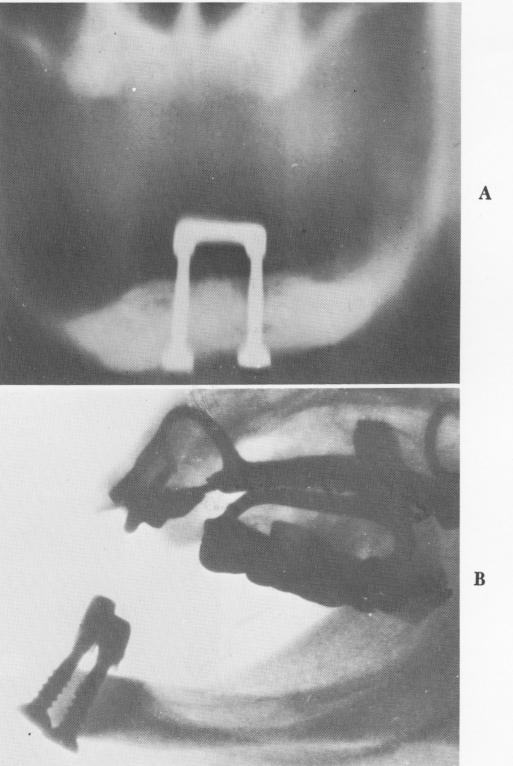

In France, Michel Chercheve, Raphael Chercheve, and Marcel Palfer-Sollier attempted a more radical approach to affixing a prosthesis. The technique was designed for the anterior region of the mandible. Long screws were inserted at the base of the mandible and passed up through it to emerge at the alveolar crest, where a conjunction bar spanned and united the screws (Fig. 5-58). The prosthesis was fashioned on the bar.

Fig. 5-58. A, In the vertical transfixation technique, screws are inserted through the lower border of the mandible up through the alveolar crest, where they are joined by a bar. In this case bone has clearly resorbed away from the bar. B, A good reason for avoiding this technique unless most of the alveolar bone has resorbed down to dense cortical bone is quite evident here. A great deal of resorption has occurred at the alveolar crest, and the heads of the screws have been driven out of the base of the mandible into the soft tissue.